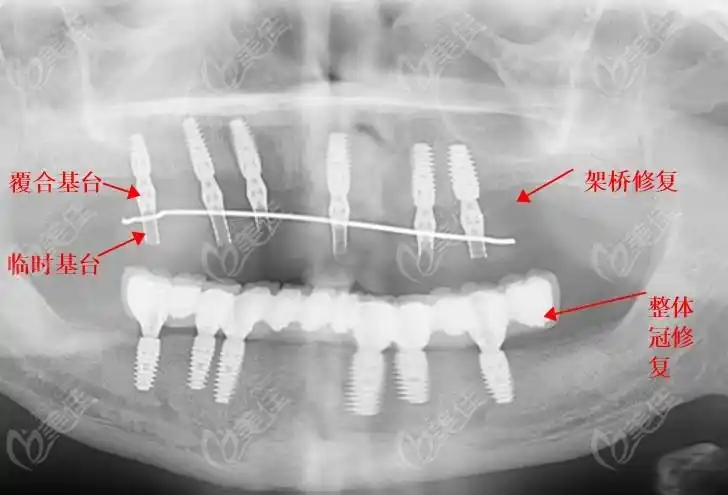

种植桥架(树脂修复)

种植马龙桥架

allon4桥架式半口即刻负重种植牙多少钱要清楚它的优缺点也要搞懂

种植桥架(hpp)